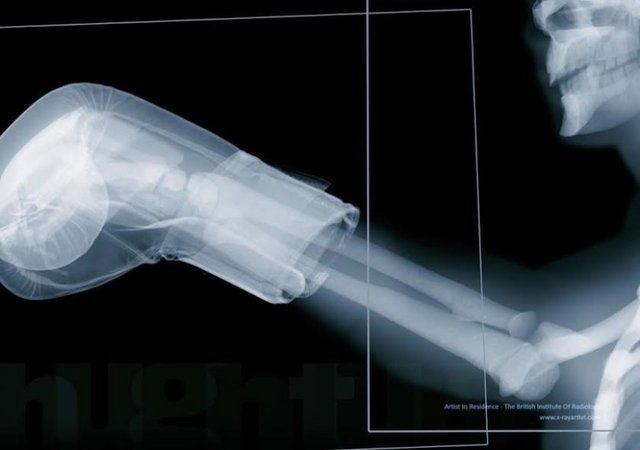

Prof.Dr. Çelenk, diğer cihazın kapı gibi bir şekli olan ve insanların içinden geçtiği cihaz olduğunu ifade ederek, "İnsanların içinden geçtiği kapıya benzer bu cihazlarda X ışınları yerine elektromanyetik alan kullanılıyor. Sadece kişinin üzerinde metal varsa tespit edip sinyal veriyor. Rahatlıkla bu güvenlik kapılarından geçilebilir. Bazen görüyorum ki özellikle hamile kadınlar, bu kapılardan geçmekten imtina ediyor, geçmek istemiyorlar. Ancak endişe edecek bir durum yok, rahatlıkla geçebilirler. Toplumda bu noktada yanlış bir algı var" diye konuştu.